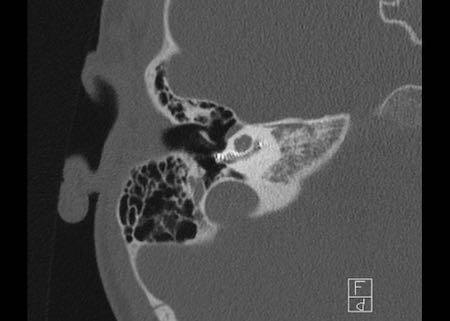

Bên trái là hình ảnh của một bé gái 2 tuổi.

Các hình ảnh từ kết quả chụp CT được thực hiện trước khi cấy ốc tai điện tử.

Quan sát thấy dị dạng nhẹ ở đỉnh ốc tai – không có sự phân tách giữa vòng thứ hai và vòng thứ ba, và trụ ốc tai xương vắng mặt.

Cống tiền đình bình thường.